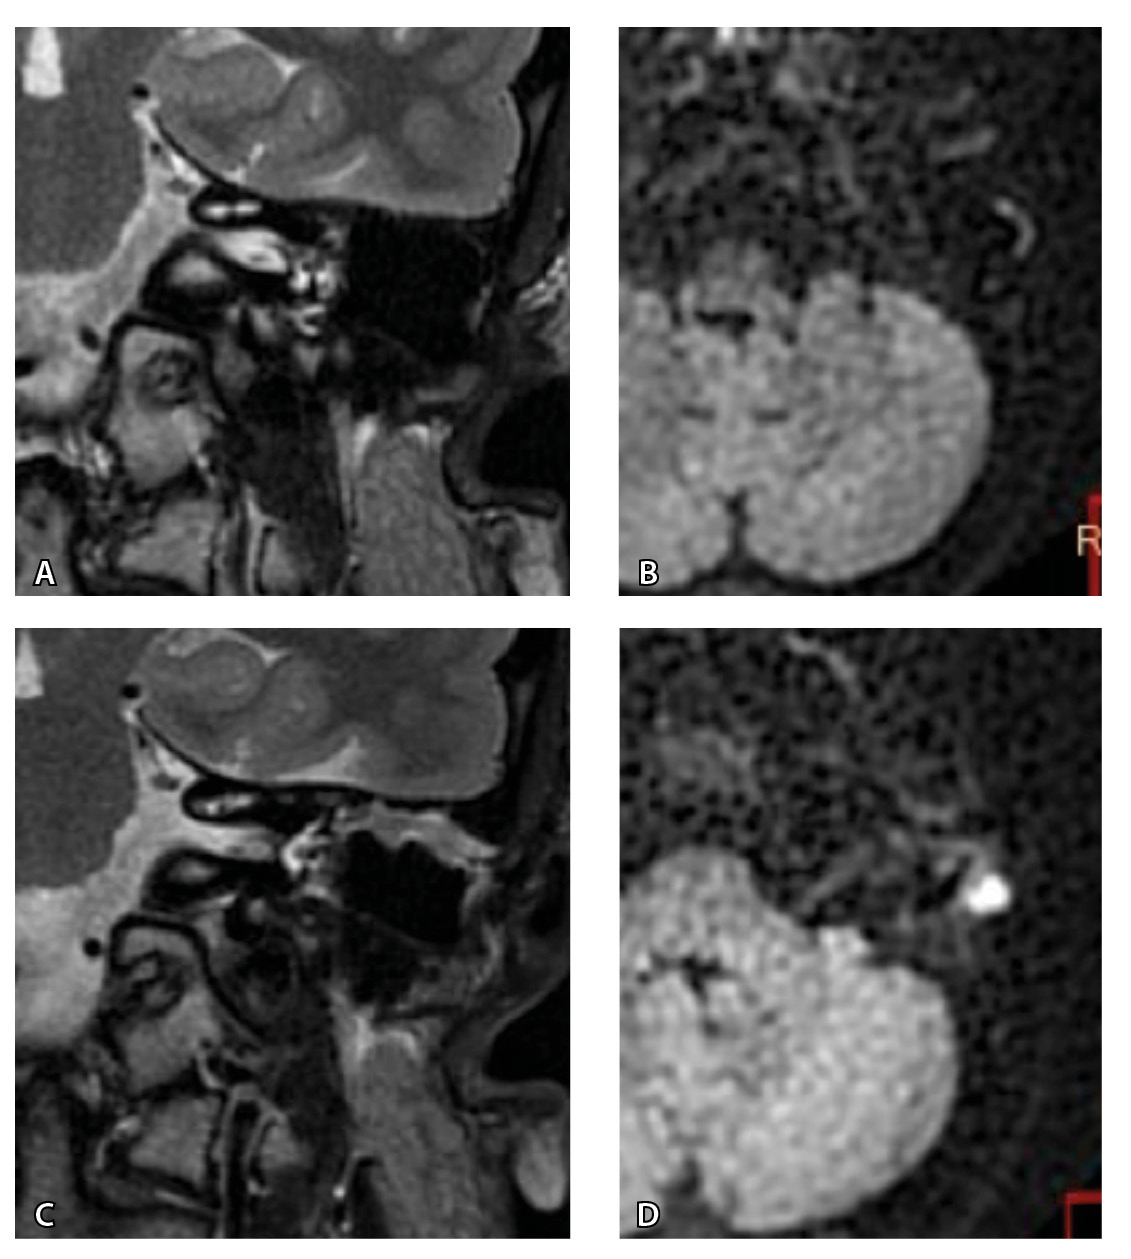

Рис. 5. При первичном послеоперационном исследовании на Т2-взвешенных изображениях во фронтальной плоскости определяется пневматизированная послеоперационная полость (А), без признаков ограничения магнитно-резонансной диффузии (Б). При контрольном исследовании – отрицательная динамика с появлением пристеночных разрастаний вдоль стенок послеоперационной полости (В), ограничивающих магнитно-резонансную диффузию (Г). Данные интерпретированы как рецидив холестеатомы. При оперативном лечении и последующей гистологии – грибковое поражение среднего уха